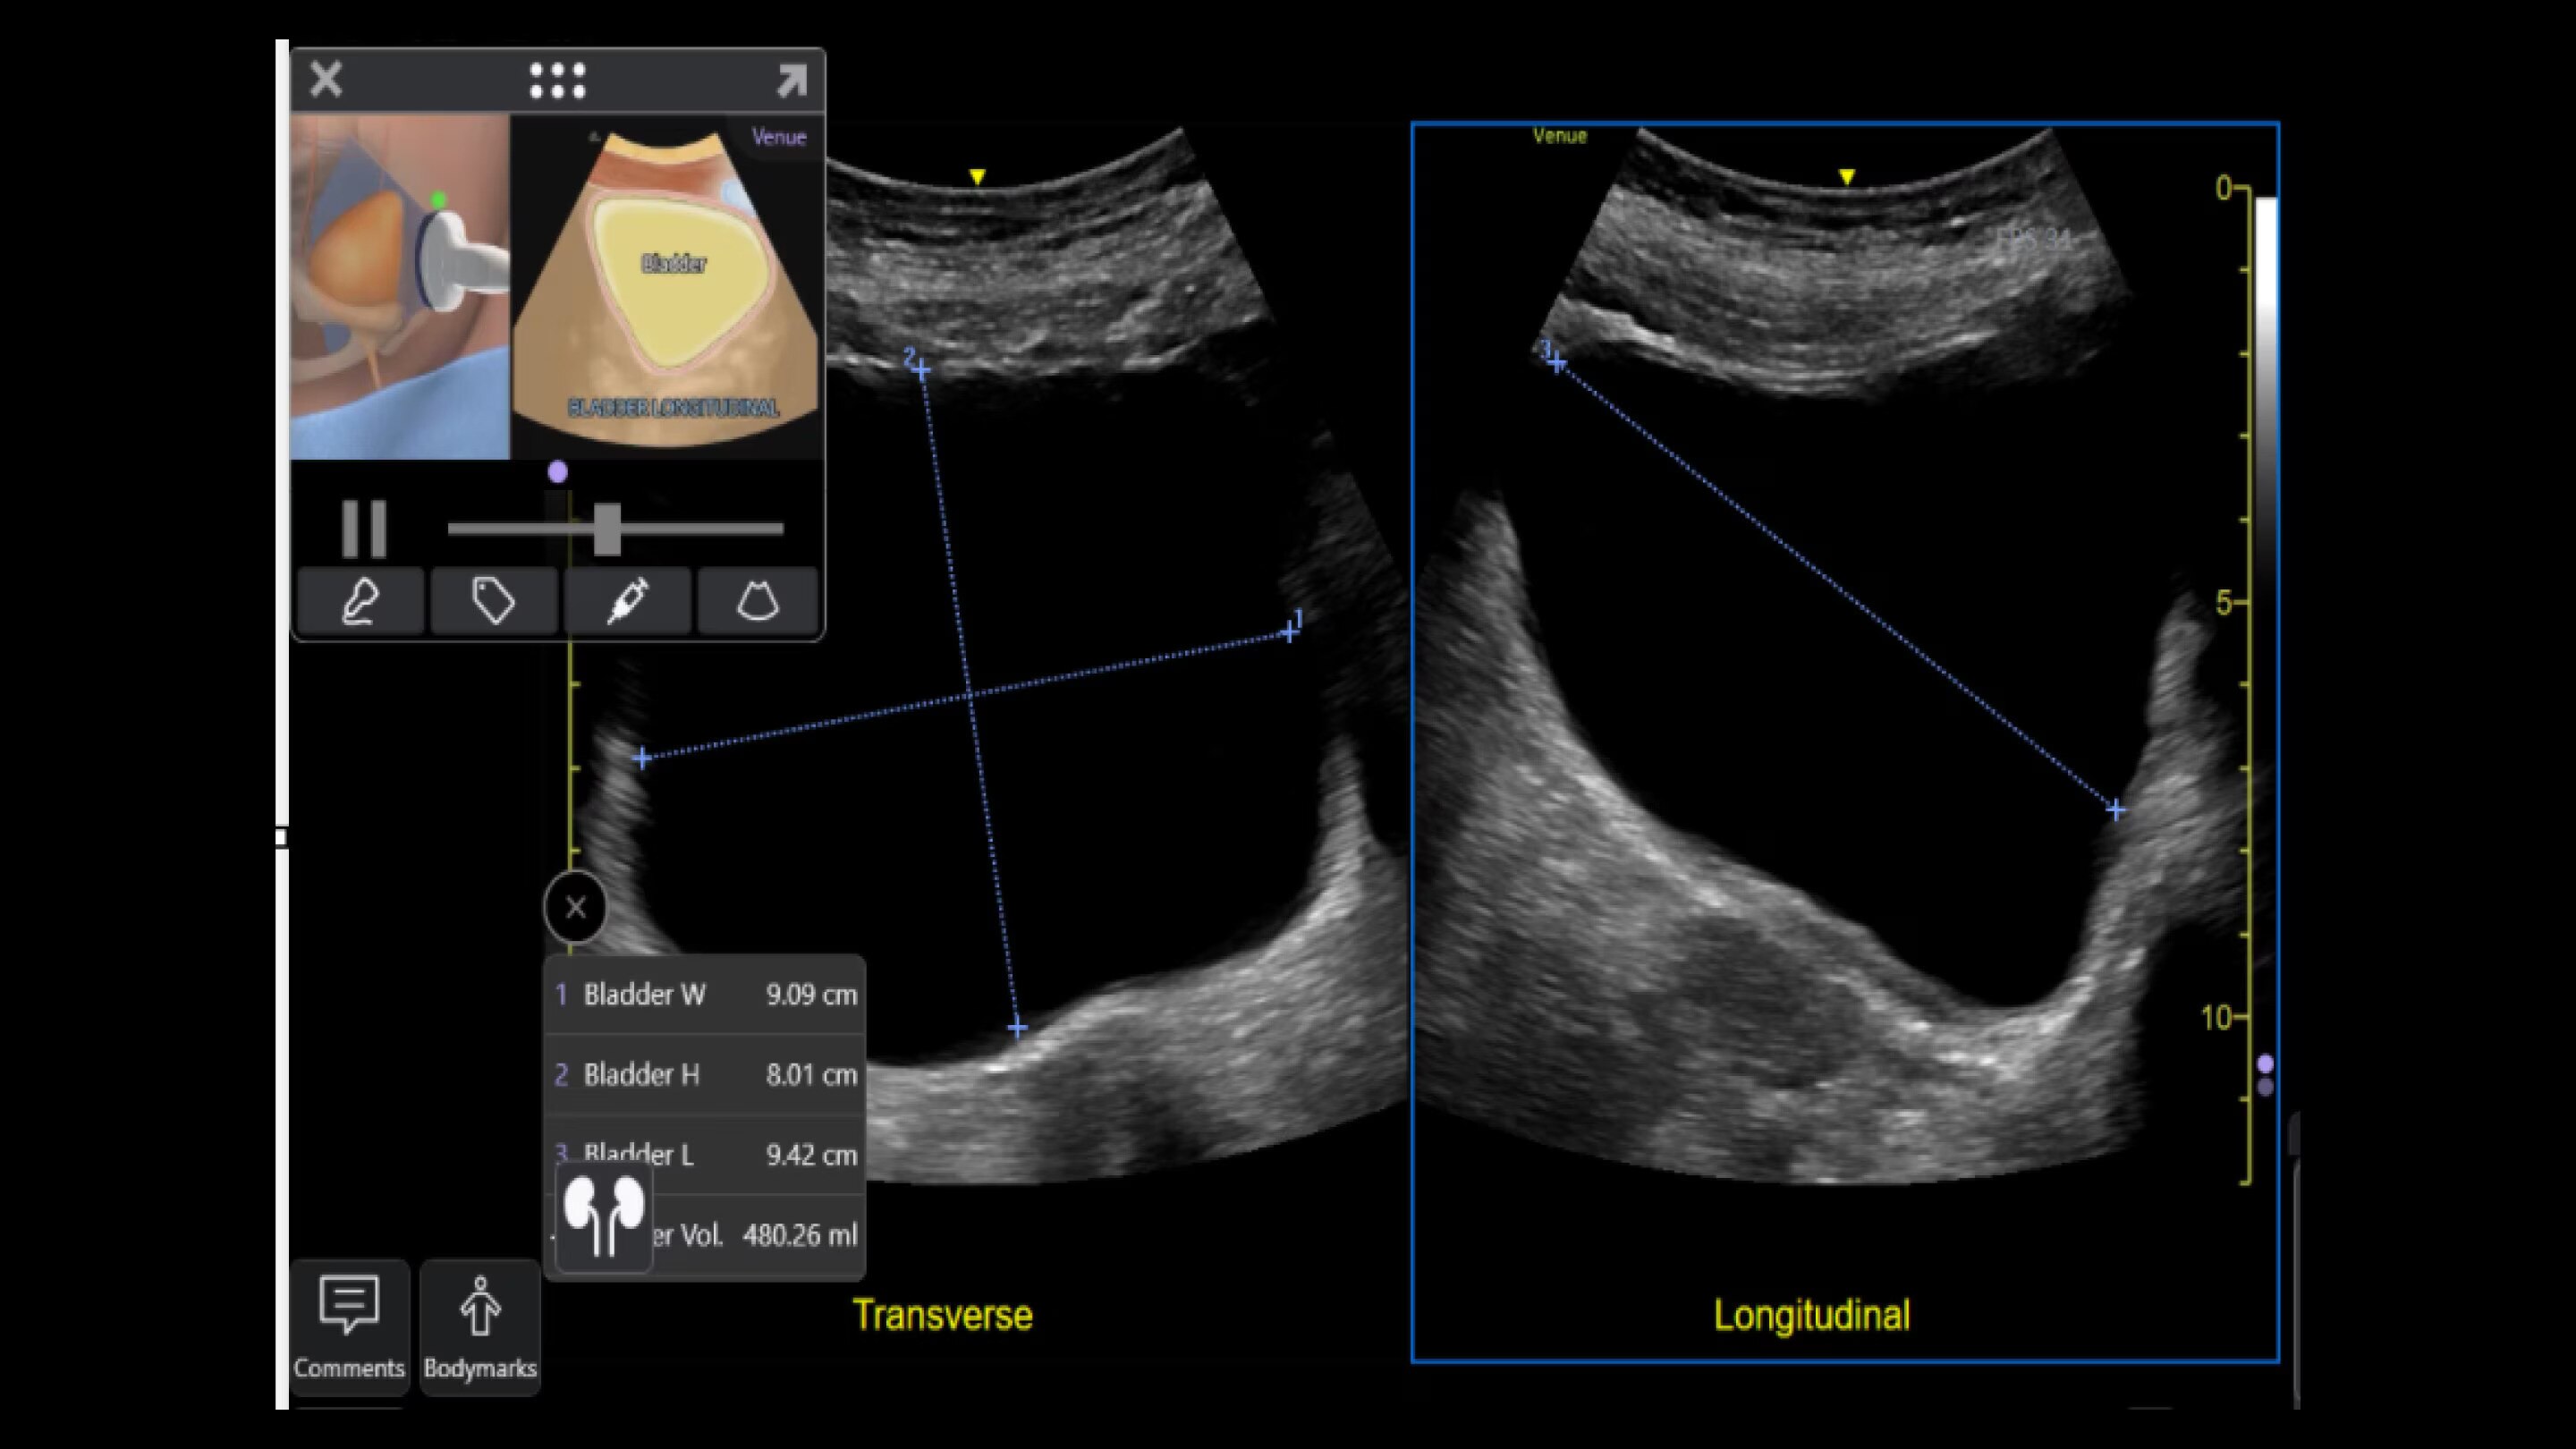

Simplify your workflow with AI-enabled clinical tools.

Helping drive consistency from user to user (whether one is an ultrasound novice or expert), Venue Fit features AI-enabled resources that help clinicians work smarter and more efficiently. Utilizing proprietary algorithms, we synthesize data from numerous patients to ensure accurate calculations for clinical confidence.